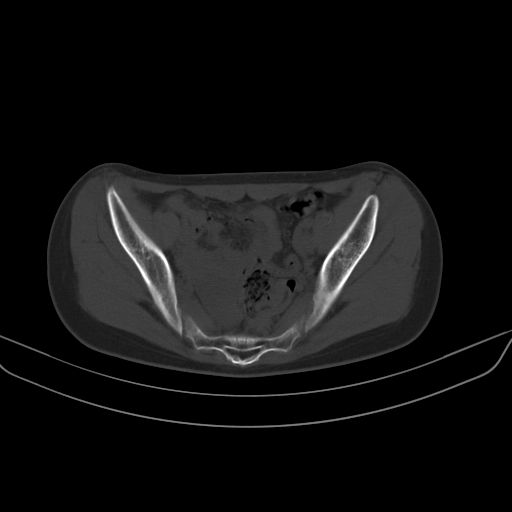

以下是引用zsl6918在2008-7-11 21:40:00的发言:[br]双侧骶髂关节骨质破坏以下三分之一为主,符合强直性脊柱炎表现

以下是引用zhangzhongshou在2008-7-11 21:41:00的发言:[br]患者是女性,hla-b27抗原(—),首先不太考虑强直性脊柱炎,建议查类风湿因子,骶髂关节改变考虑类风湿性关节炎可能性大,建议进一步检查。